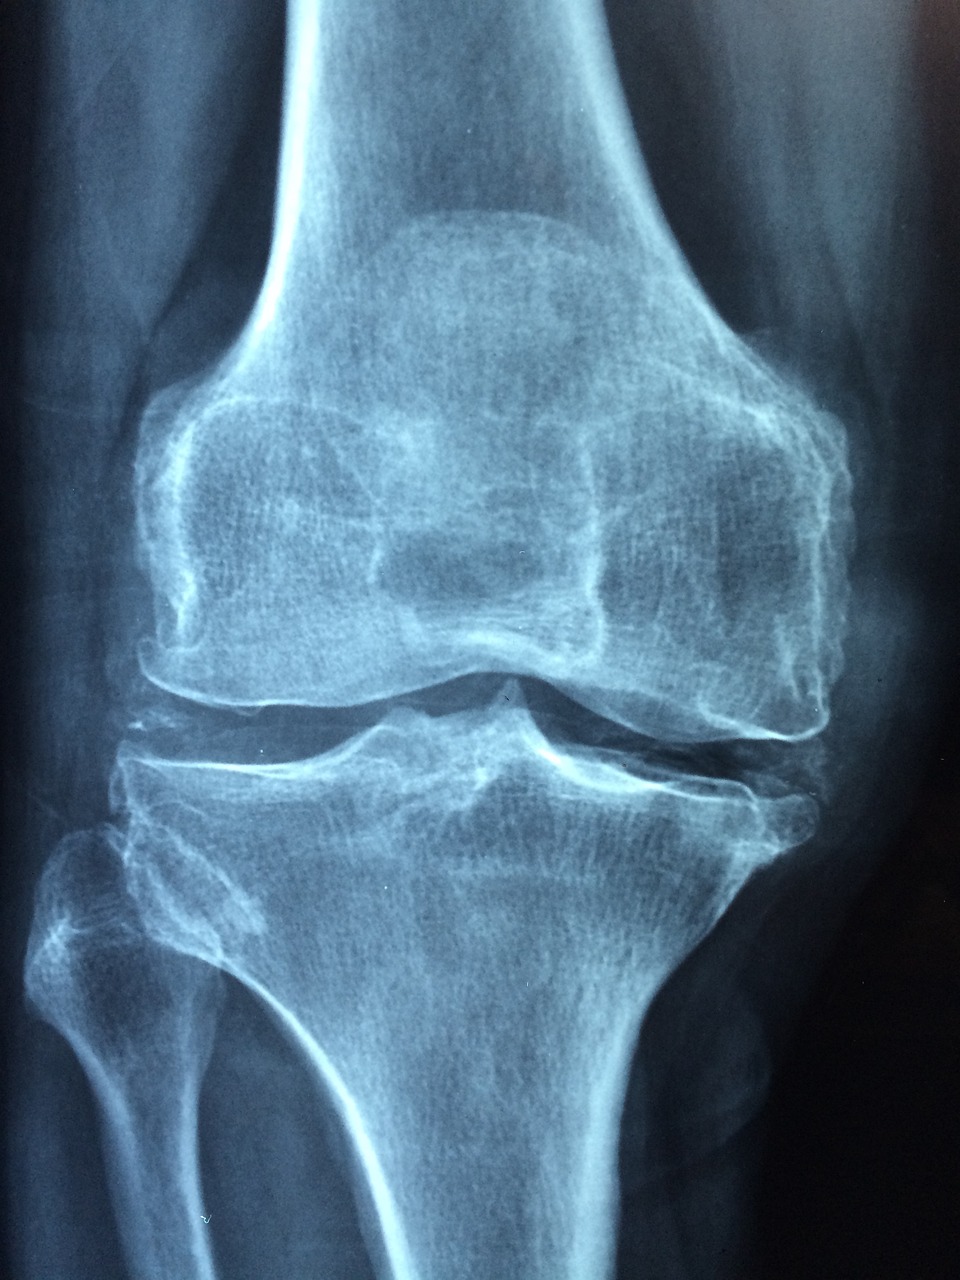

무릎 인공관절 수술을 받은 후 통증이 남아 있는 건 자연스러운 회복 과정일 수 있습니다.

하지만 특정한 신호가 동반된다면 단순한 수술 후 통증이 아닌 무릎 인공관절 수술 후 염증일 가능성도 있습니다.

1️⃣ 무릎 인공관절 수술 후 정상적인 회복 과정

✅ 무릎 인공관절 수술 후엔 어느 정도의 통증과 부기가 따라오는 것이 일반적입니다.

수술 부위 조직이 회복되는 동안 통증은 보통 2~6주 사이 점차 줄어들며,

무릎의 운동 범위도 점점 회복되게 됩니다.

● 수술 후 12주차: 통증은 있지만 움직임이 늘고 실밥 제거, 간헐적 얼음찜질 권장

● 3~6주차: 가벼운 재활운동 시작, 계단이나 평지 보행이 가능해짐

● 6주차 이후: 통증과 부기 대부분 감소, 관절 기능이 일상생활 수준으로 회복

💡 이 시기에도 통증이 점점 심해지거나 다시 부어오른다면 ‘무릎 인공관절 수술 후 염증’ 가능성을 꼭 생각해봐야 합니다.